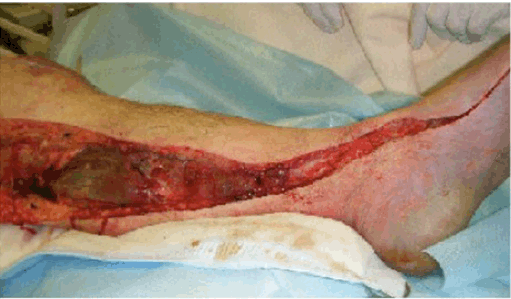

On day-4, the skin of the left lower leg abruptly turned white and purpura developed. Doppler ultrasound was unable to detect blood flow in the left dorsalis pedis artery, and a CT scan showed severe stenosis of the left common iliac and femoral arteries. The patient's CK level had risen to 60,000 IU/L. The clinical manifestations, laboratory findings, and results of radiological imaging were suggestive of acute limb ischemia. We performed angiography, which revealed significant stenosis of the left common iliac artery (Figure 2); this finding was compatible with acute limb ischemia. We discussed whether or not we should perform revascularization because we did not know the precise time of onset of the limb ischemia. We reached the decision to insert a self-expanding stent into left common iliac artery and to perform a counter-incision (Figure 3) because the intracompartmental pressure of the left lower extremity was 70 mmHg. The patient's scrotum had also become swollen and erythematous on day-4, and its color had changed to purple on day-5 (Figure 4). We suspected Fournier gangrene and consulted urologists accordingly. Puncture of the scrotum revealed a serous, yellow, clear fluid, which was compatible with hydrocele testis, not Fournier gangrene. Despite the counter-incision, eight days after the patient's admission the color of his left lower extremity had not improved and the CK had risen rapidly further to 1, 500, 000 U/L. We considered other differential diagnosis including purpura fulinans caused by Streptococcus pneumonia, Streptococcus pyogenes, Vibrio vulnificus, and Neisseria meningitides. We therefore performed major amputation above the hip joint. The patient's general condition, including his vital signs, disseminated intravascular coagulation score, and oxygenation, improved temporarily after this intervention.

Figure 3: We reached a decision to insert a self-expanding stent into the left common iliac artery and to perform a counter-incision Because the intracompartmental pressure of the left lower extremity was 70 mmHg.